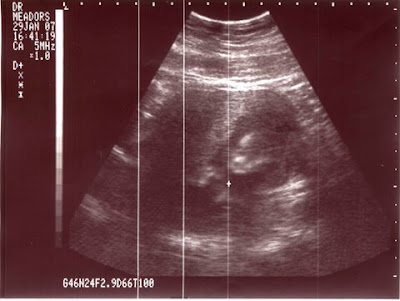

We finally scanned our ultrasound pictures into the computer. So, I wanted to share a couple with you. I know it’s a little late as our 8 month check-up is tomorrow. Oh, well.

Here’s our sweet little girl:

January 2007

March 2007